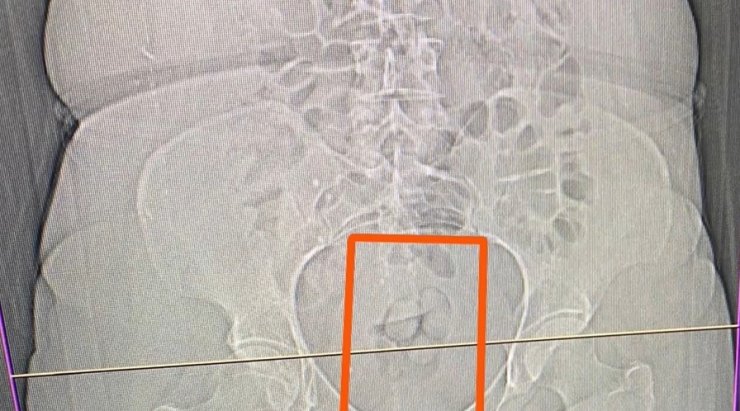

S.S. isimli şahısın şüpheli görülmesi üzerine çekilen tomografi neticesinde şahsın midesinde yabancı maddeler tespit edildi. Yapılan iç beden muayenesi sonucunda ise şahıstan 21,39 gram metamfetamin maddesi ele geçirildi.